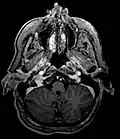

Glomus jugulare tumor

Glomus jugulare tumor -

_in_a_patient_with_VHL.jpg) Ectopic functional paraganglioma (glomus jugulare) in a patient with VHL. T2 weighted MRI at the same location demonstrates a high signal mass consistent with a paraganglioma. Extra adrenal paragangliomas can be found in VHL (arrow).

Ectopic functional paraganglioma (glomus jugulare) in a patient with VHL. T2 weighted MRI at the same location demonstrates a high signal mass consistent with a paraganglioma. Extra adrenal paragangliomas can be found in VHL (arrow). -